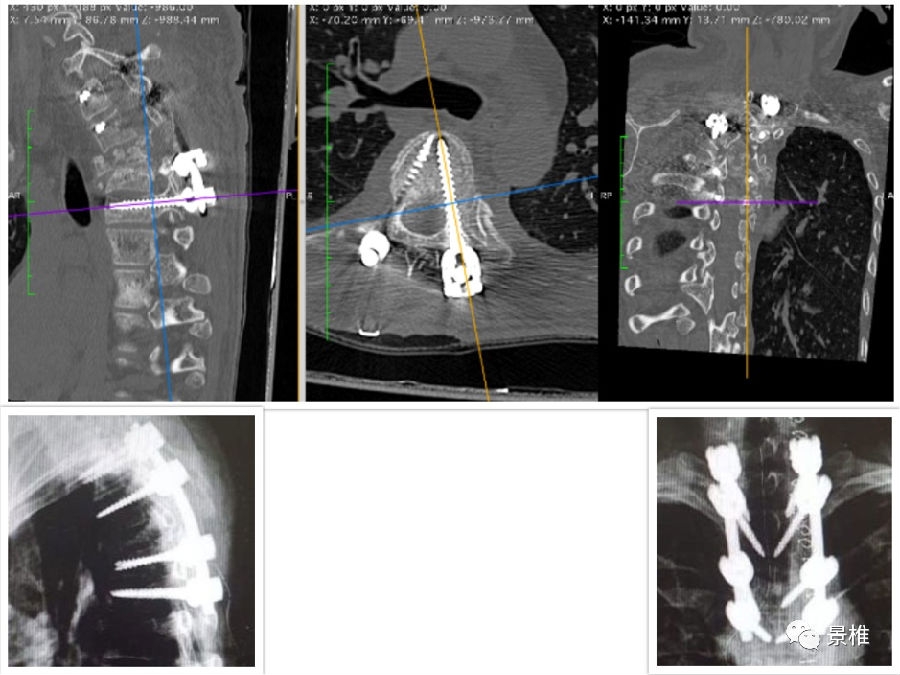

已有学者总结出经验:胸腰椎椎弓根置钉的头尾倾角度,与上下相邻关节突关节所在的平面垂直。

君子性非异,善假于物焉。此时利用直角器械,比如甲状腺拉钩、事先折好角度的克氏针等等:短头贴在相邻两个关节突上,那长杆的指向就是钉道的走行。

本人亲测,术中用甲钩比划,好像有些繁琐,不如透视后直接估计角度来的利索。当然借助甲钩定向法钉道走向可能会更完美。